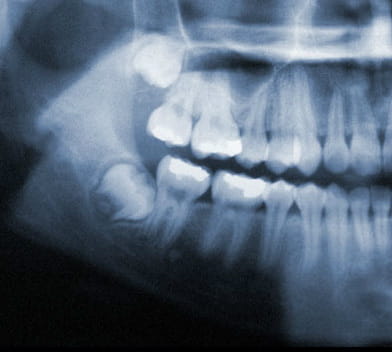

Wisdom Tooth Positions

Wisdom teeth under ideal circumstances should grow in straight like any other tooth. However, it is common for wisdom teeth to become impacted inside the jaw or just under the gums. If this occurs, your wisdom teeth should be removed.

Common Impactions:

- Horizontal Impaction

- Angular Impaction

- Vertical Impaction

- Soft Tissue Impaction

Wisdom teeth also known as third molars are the last teeth to erupt into the mouth. Wisdom teeth typically appear around a person's mid-twenties but can erupt much later. If wisdom teeth don't have enough space symptoms can occur. The wisdom teeth may only partially erupt or might not come through at all. Dentists designate wisdom teeth 'impacted' if they are wholly or partly blocked from eruption into the mouth. The tooth may lie at an angle and remain tipped against an adjacent tooth. Impacted wisdom teeth can cause problems like pain and swelling; The mouth could ache when stretched open wide or it may be difficult to open your mouth. Tenderness when chewing and biting may occur. Earaches may develop from the spread of pain in the mouth. Symptoms may be intermittent but can begin anytime without warning. If you are experiencing symptoms, it is best to get treatment 'usually removal' as soon as you can to avoid potentially expensive and painful complications.